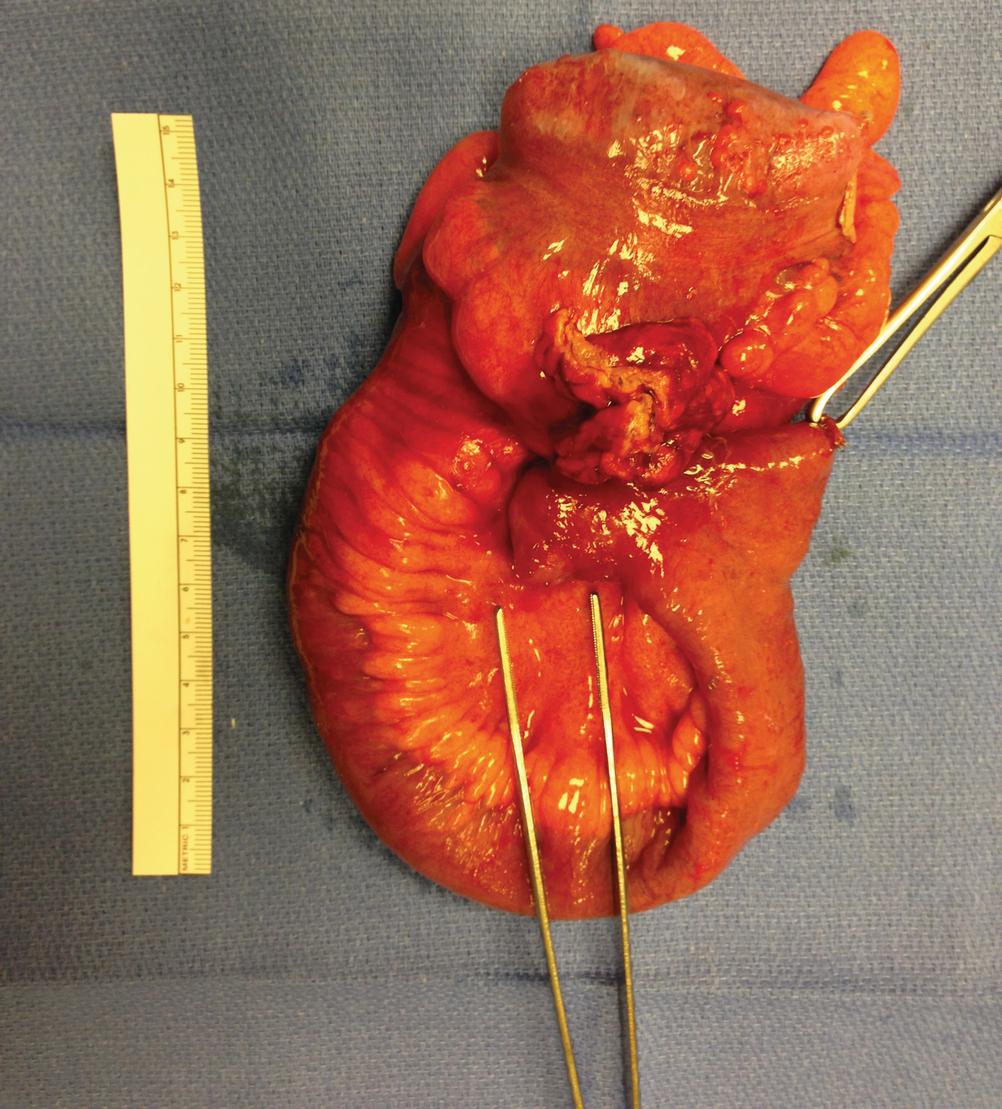

Fig. 1.20

Descriptive text is not available for this image

Perforated Meckel’s diverticulum with fistula to the ileum